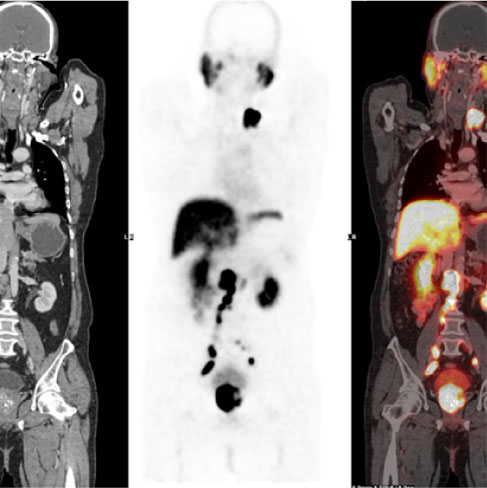

PSMA (Prostate-Specific Membrane Antigen) is a membrane glycoprotein that is an over-expressed manifold in prostate cancers and the expression increases with tumour aggressiveness, androgen independence, metastatic disease and disease recurrence.

PSMA PET Scan for prostate cancer is a prostate cancer-specific target diagnostic scan that provides both better sensitivity & high specificity at diagnosis for disease site localisation & improves detection at an earlier time point than with anatomical imaging techniques even at low PSA levels.